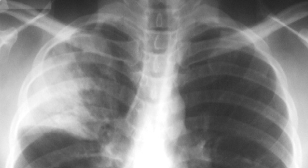

Air-space filling (consolidation) in the right upper lobe is due to pneumonia